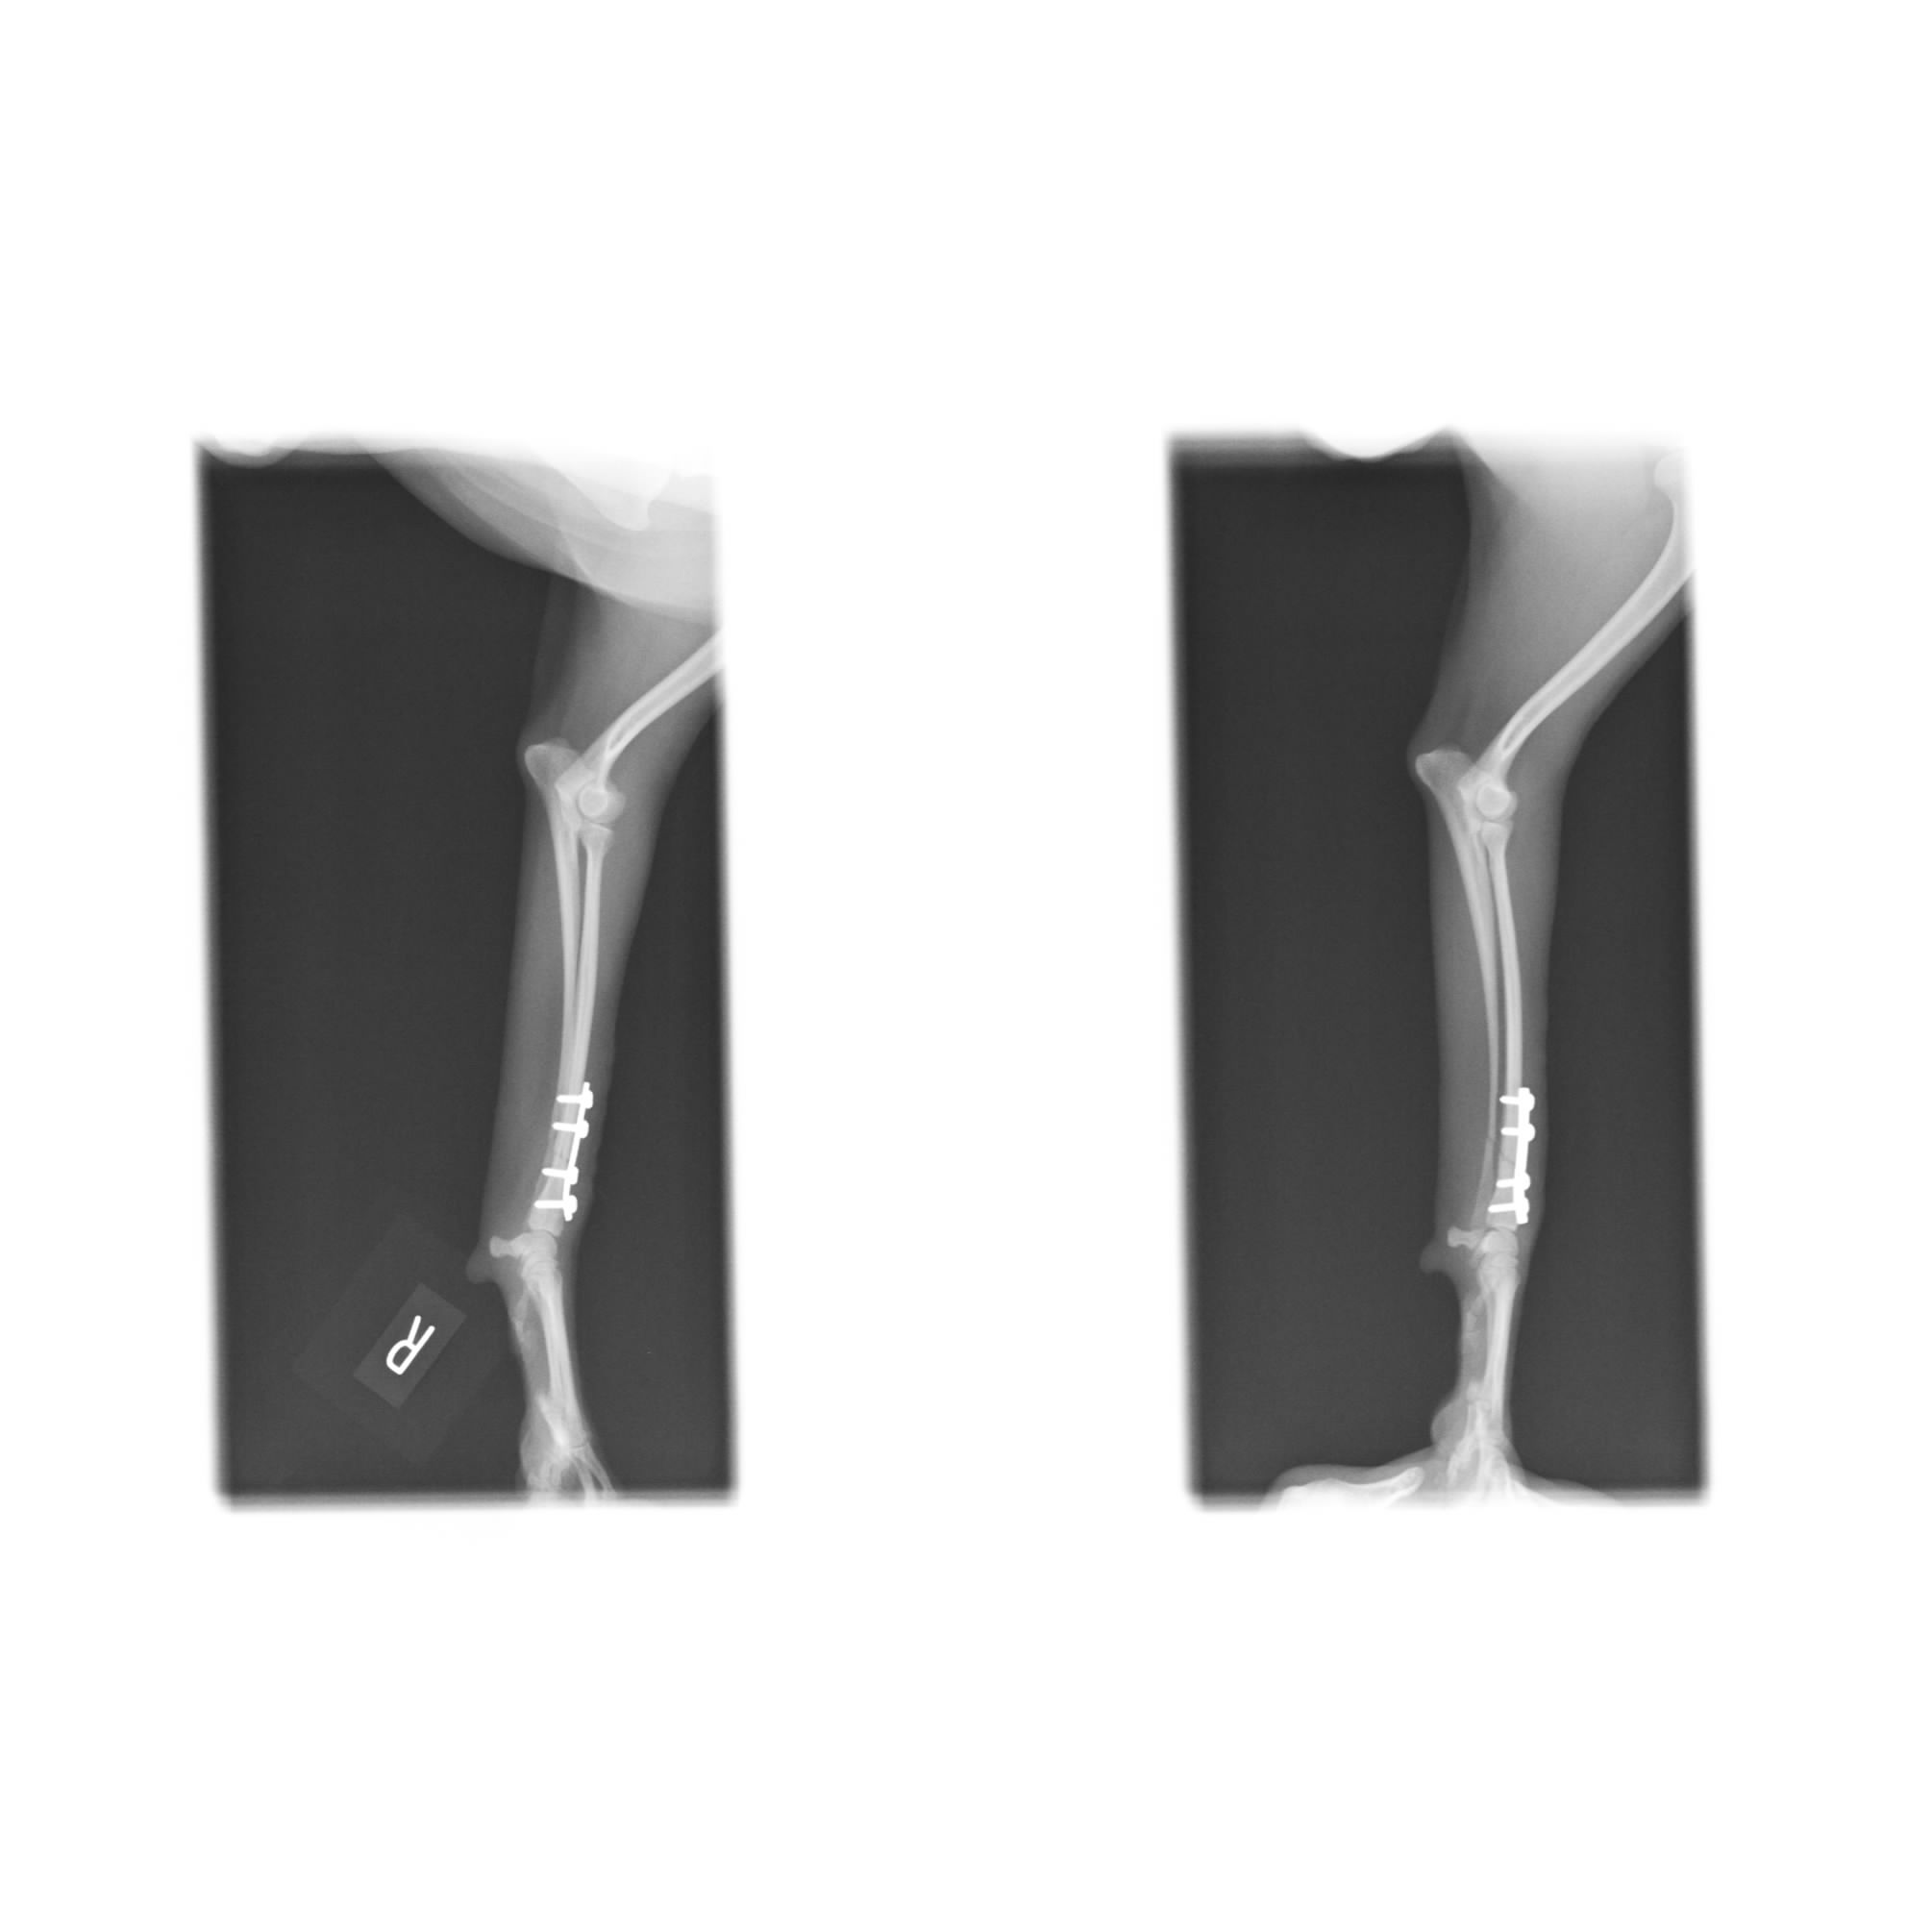

本日は両方の前足を骨折してしまった体重2kg、骨の厚み3、4mmのポメラニアンちゃんの治療をご紹介させて頂きます![]()

全く同じように見えますが、左右共に骨折してしまったレントゲン写真です![]()

骨の厚みは女性の小指よりも細いのではないでしょうか。

骨折線を慎重に合わせ、元通りの形・角度になるようにプレートをインプラントします。

非常にキレイにプレート固定出来ました![]()